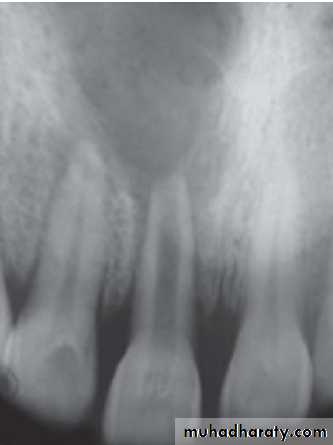

Radiographic Features

• Radiolucency at root and adjacent bone• Irregular shortening or thinning of root

• Loss of Lamina dura.